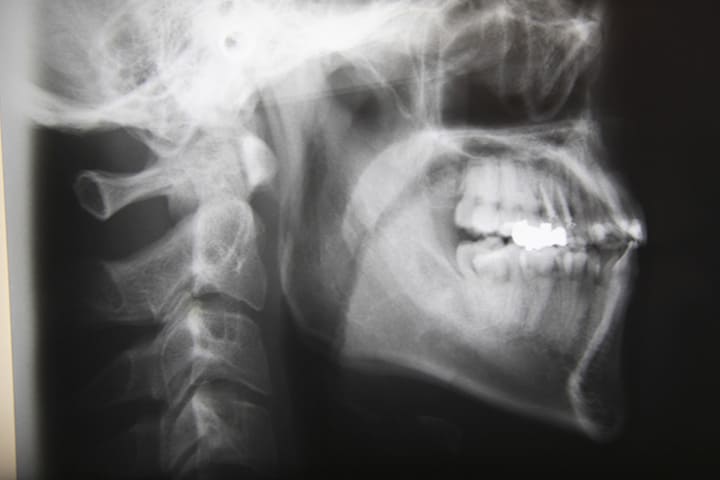

セファロ分析による診断

いびきの診断にはさまざまな方法がありますが、当院ではX線写真を利用した「セファロ分析」を採用しています。セファロ分析では、頭部をレントゲン撮影することで患者さんの顎など口周りの骨格や気道・舌の大きさといった軟組織を分析することができます。

頭部の骨の形を確認することで、いびきや睡眠時無呼吸症候群が起こりやすいかどうかもチェックすることができます。